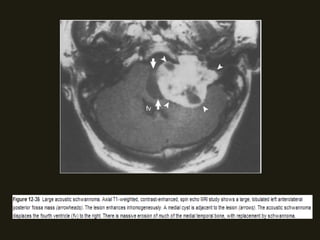

SCHWANOMAS ACÚSTICOS

• Tumores benignos do VIII PC ocorrem no CAI/ângulo

cerebelopontino, surgindo na junção das células da glia com

as de Schwann; Associação com neurofibromatose tipo 2;

• Sintomas dependem da localização do tumor (há compressão

dos nervos coclear e vestibular (CAI) – zumbido, diminuição

acuidade auditiva;

• RM método de escolha (nervo espessado e com realce pelo

contraste; podem ser císticos;); diferencia schwanomas

pequenos dos nervos normais;

NEOPLASIAS BENIGNAS

• Podem ser massas pequenos ou grandes;

• Grandes – distorção da fossa posterior; hérnia de tronco,

hidrocefalia e compressão do IV ventrículo;

• TC alta resolução – mostras alterações ósseas do CAI, porus

acusticus e cápsula óptica; Assimetria dos CAI > 2mm sugere

MASSA!!